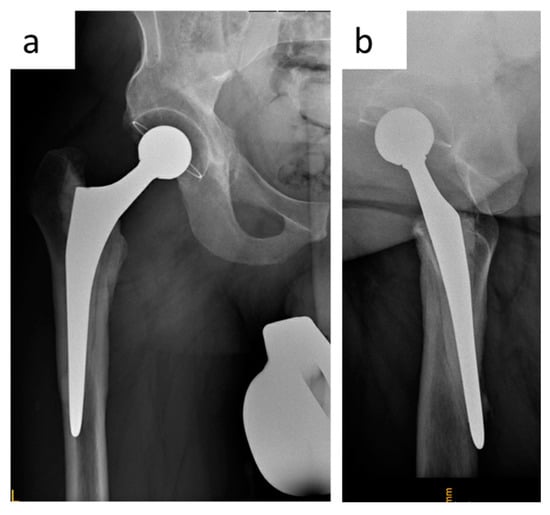

2.3.3. Clinical Case

2.3. Novel Surgical Technique: A Monocortical Screw for Preventing Trochanteric Escape

2.3.1. The Surgical Technique